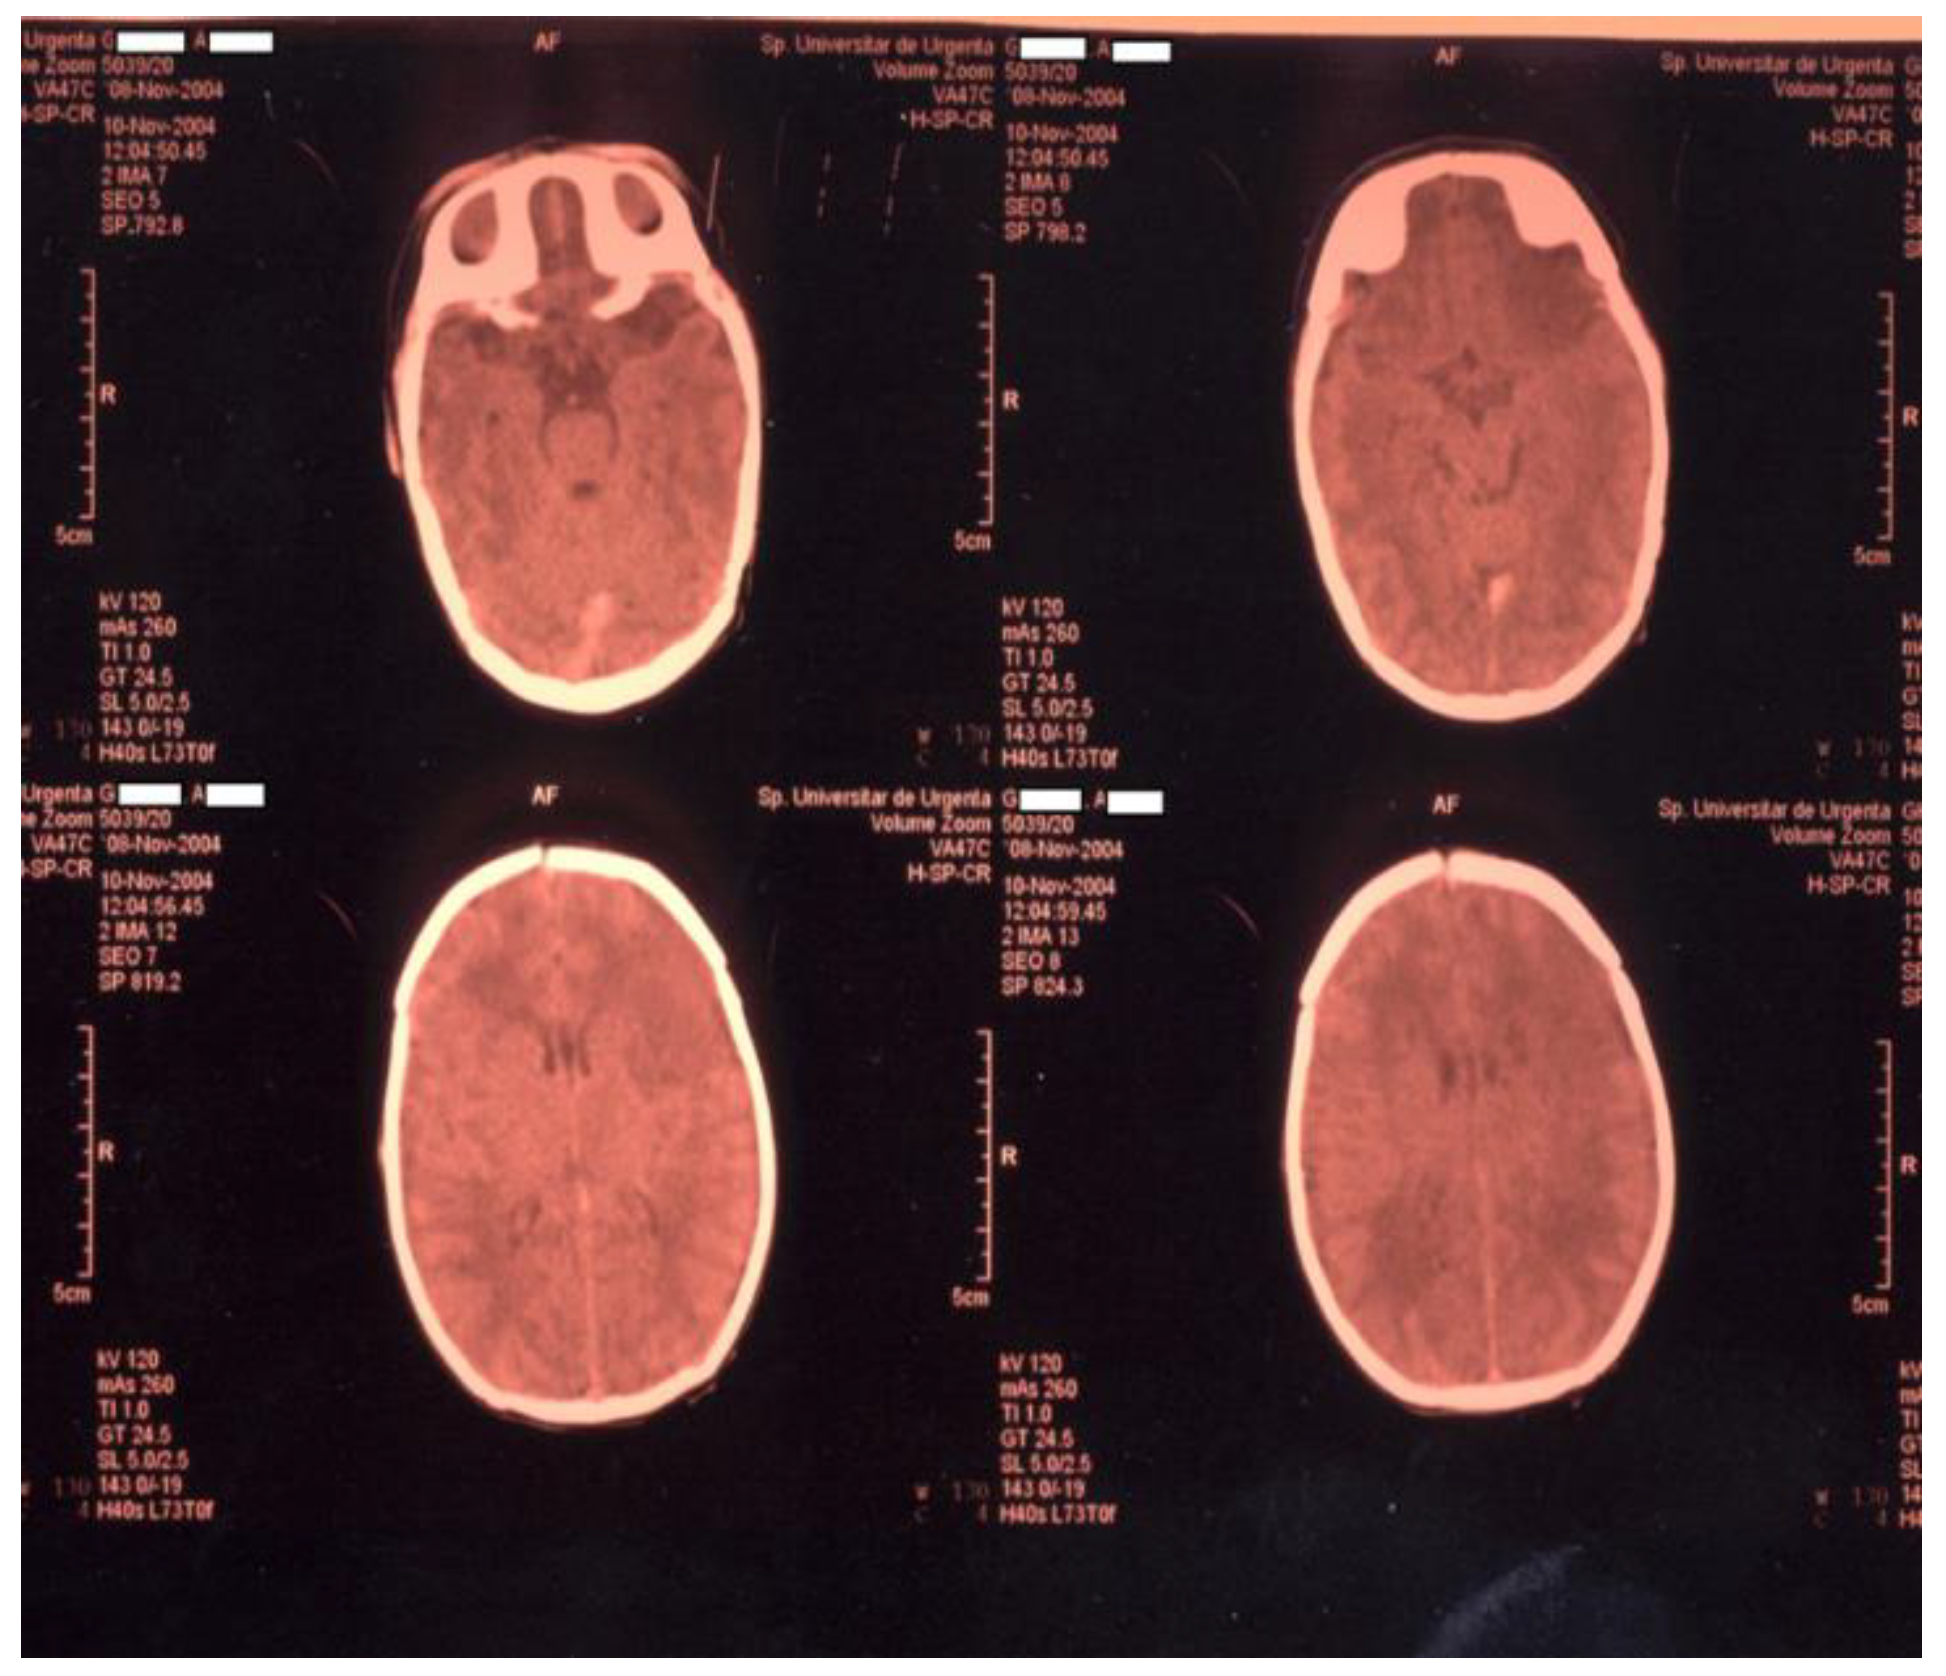

Newborn #1 was born at 36-37 weeks of gestation, 3000g/50cm, female, first child of a healthy mother, from an uneventful pregnancy, extracted by caesarean section for premature rupture of membranes, Apgar score 9, smooth transition to the extrauterine environment, normal clinical examination after birth; baby develops at 36 hours of life tonic-clonic seizures of the left hemibody associated with cyanosis, apnea and bradycardia and was admitted into the NICU, was tested for metabolic causes of the seizures, lumbar puncture and inflammatory panel and bacteriologic tests were performed and Phenobarbital was started. Because of recurrent apneic spells respiratory support was initiated and imagistic investigations were ordered. Head ultrasonography raised suspicion of a large right frontal-parietal infarction confirmed later through Magnetic Resonance Imaging (MRI). Echocardiography revealed no abnormalities. Laboratory tests were all within normal limits except a mild thrombocytopenia (105000/mmc).

Figure 1. CT examination for newborn #1.

Figure 2. MRI examination for newborn #1 confirms large right frontal-parietal infarction.

Within differential diagnosis, we considered: maternal chorioamnionitis, hypoxic ischemic encephalopathy, vascular malformations, cardiac lesions, trauma and a hereditary coagulopathy. We performed molecular tests for both mother and infant that revealed heterozygote G1691A mutation on the gene responsible for synthesising factor V Leiden. A less frequent condition related to ischemic stroke in children and adults is sickle cell disease, although not documented in newborns, was also excluded [24,25].

Most perinatal strokes are ischemic and affect the left cerebral hemisphere, in the territory of the middle cerebral artery [26]. In our case, the infarct was in the frontal-parietal right cortical region. We could not identify in this case any of the supplementary risk factors for thrombosis.